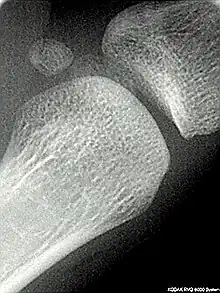

Les os sésamoïdes (du grec, sêsamoeides : qui ressemble au sésame) sont de petits os que l’on trouve principalement près des articulations et dans l’épaisseur de tendons[1]. La formation des os sésamoïdes est différente de celle des autres os, puisque ce sont des vestiges de ligaments calcifiés, c’est pourquoi ils ne sont pas tous considérés comme partie intégrante du squelette humain.

La fracture la plus fréquente des os de type sésamoïde est une fracture d’avulsion.

Un os sésamoïde peut être sujet à une inflammation entraînant une sésamoïdite[9]. C'est une affection fréquente des pieds chez les danseurs.

La maladie de Renander est une atteinte des sésamoïdes du premier métatarsien qui peut apparaître au cours de la croissance ou chez le jeune adulte.

Les os sésamoïdes ont généralement un apport sanguin très limité, ce qui les rend sujets à des ostéonécroses par manque d'apport sanguin et qui sont difficiles à traiter[10].